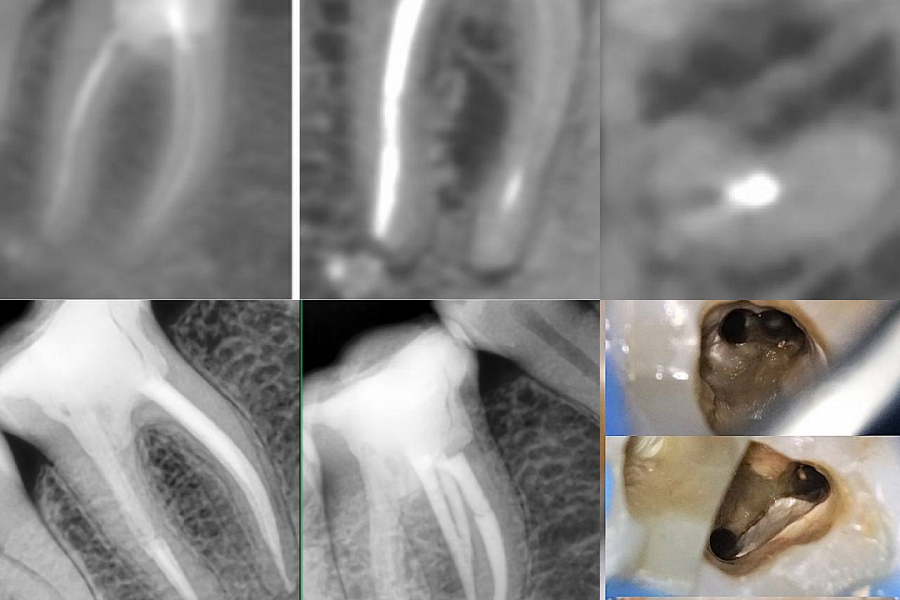

Этапы лечения

Лечение каналов под микроскопом